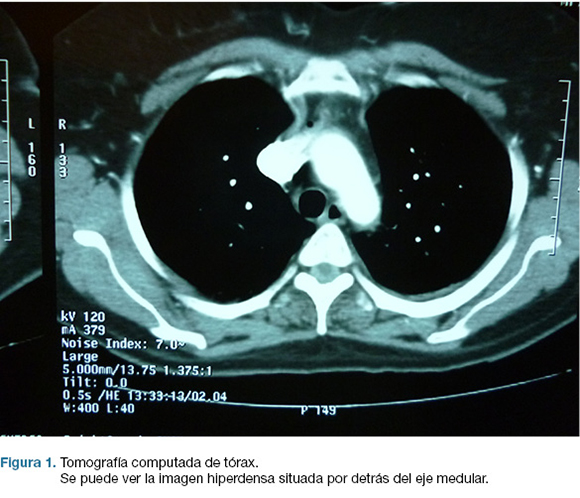

Con planteo de disección de aorta, se realiza TC de tórax que descarta la misma. La visualización cuidadosa de las imágenes permitió ver una colección intrarraquídea hemática, posterior al eje medular y extendida de T4 a T6 (figura 1). Se interviene de emergencia con diagnóstico de hematoma intrarraquídeo extramedular.